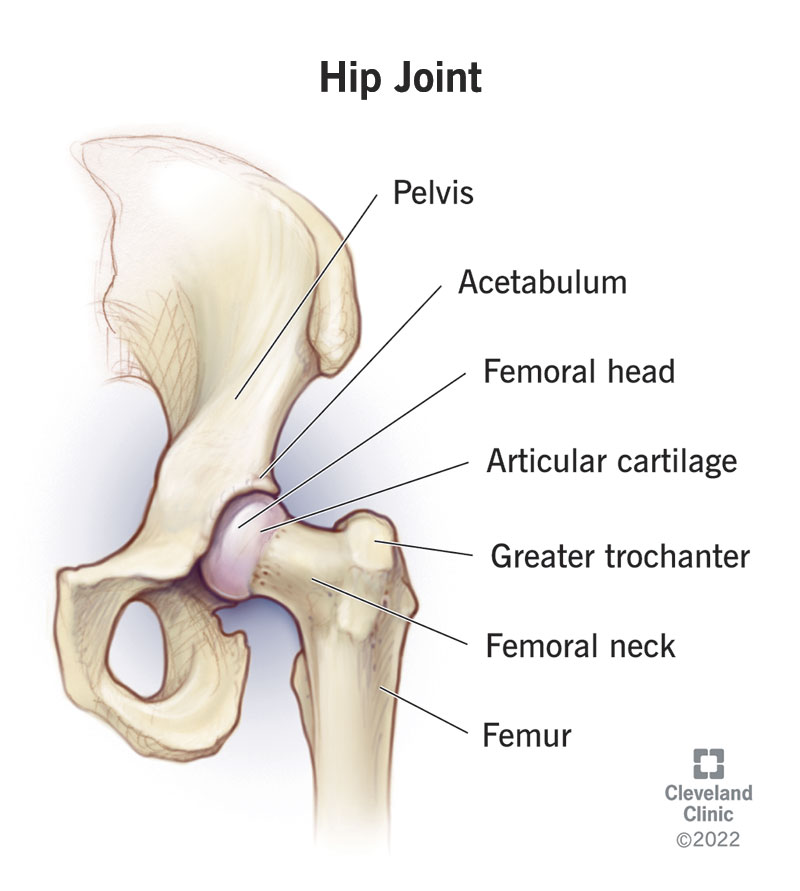

The hip joint is one of the most important joints in the human body, as it supports the weight of the body in both standing and movement.

It is a ball-and-socket type joint that allows smooth and stable motion in multiple directions.

The hip joint is made up of two main bones:

Femur (thigh bone)

the upper bone of the leg

Pelvis (hip bone)

the socket part that holds the head of the femur Photo of Hip Joint with Bone mark